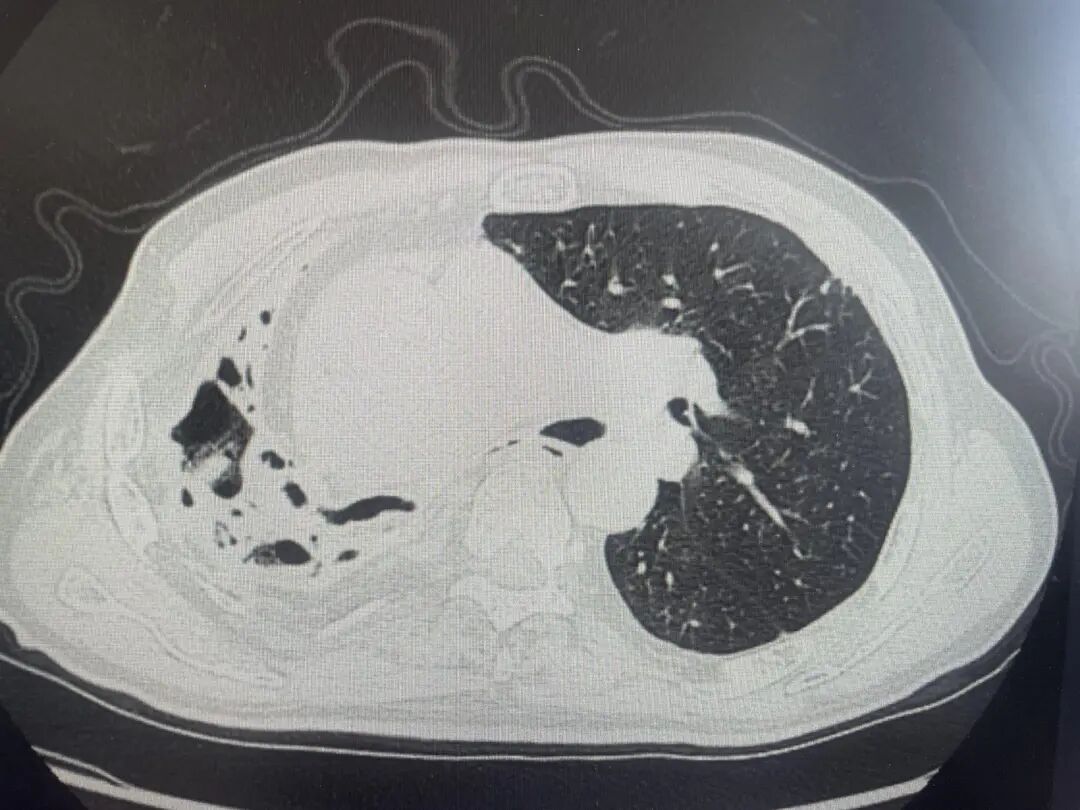

肺部CT结果显示,王大伯的右肺已严重毁损,呈现出典型的蜂窝状改变,肺功能受损严重。凭借丰富临床经验,医生高度怀疑是特殊致病菌感染,随即通过支气管镜肺泡灌洗,结合NGS高通量测序查找病原体。

肺部CT提示右肺毁损、蜂窝状改变